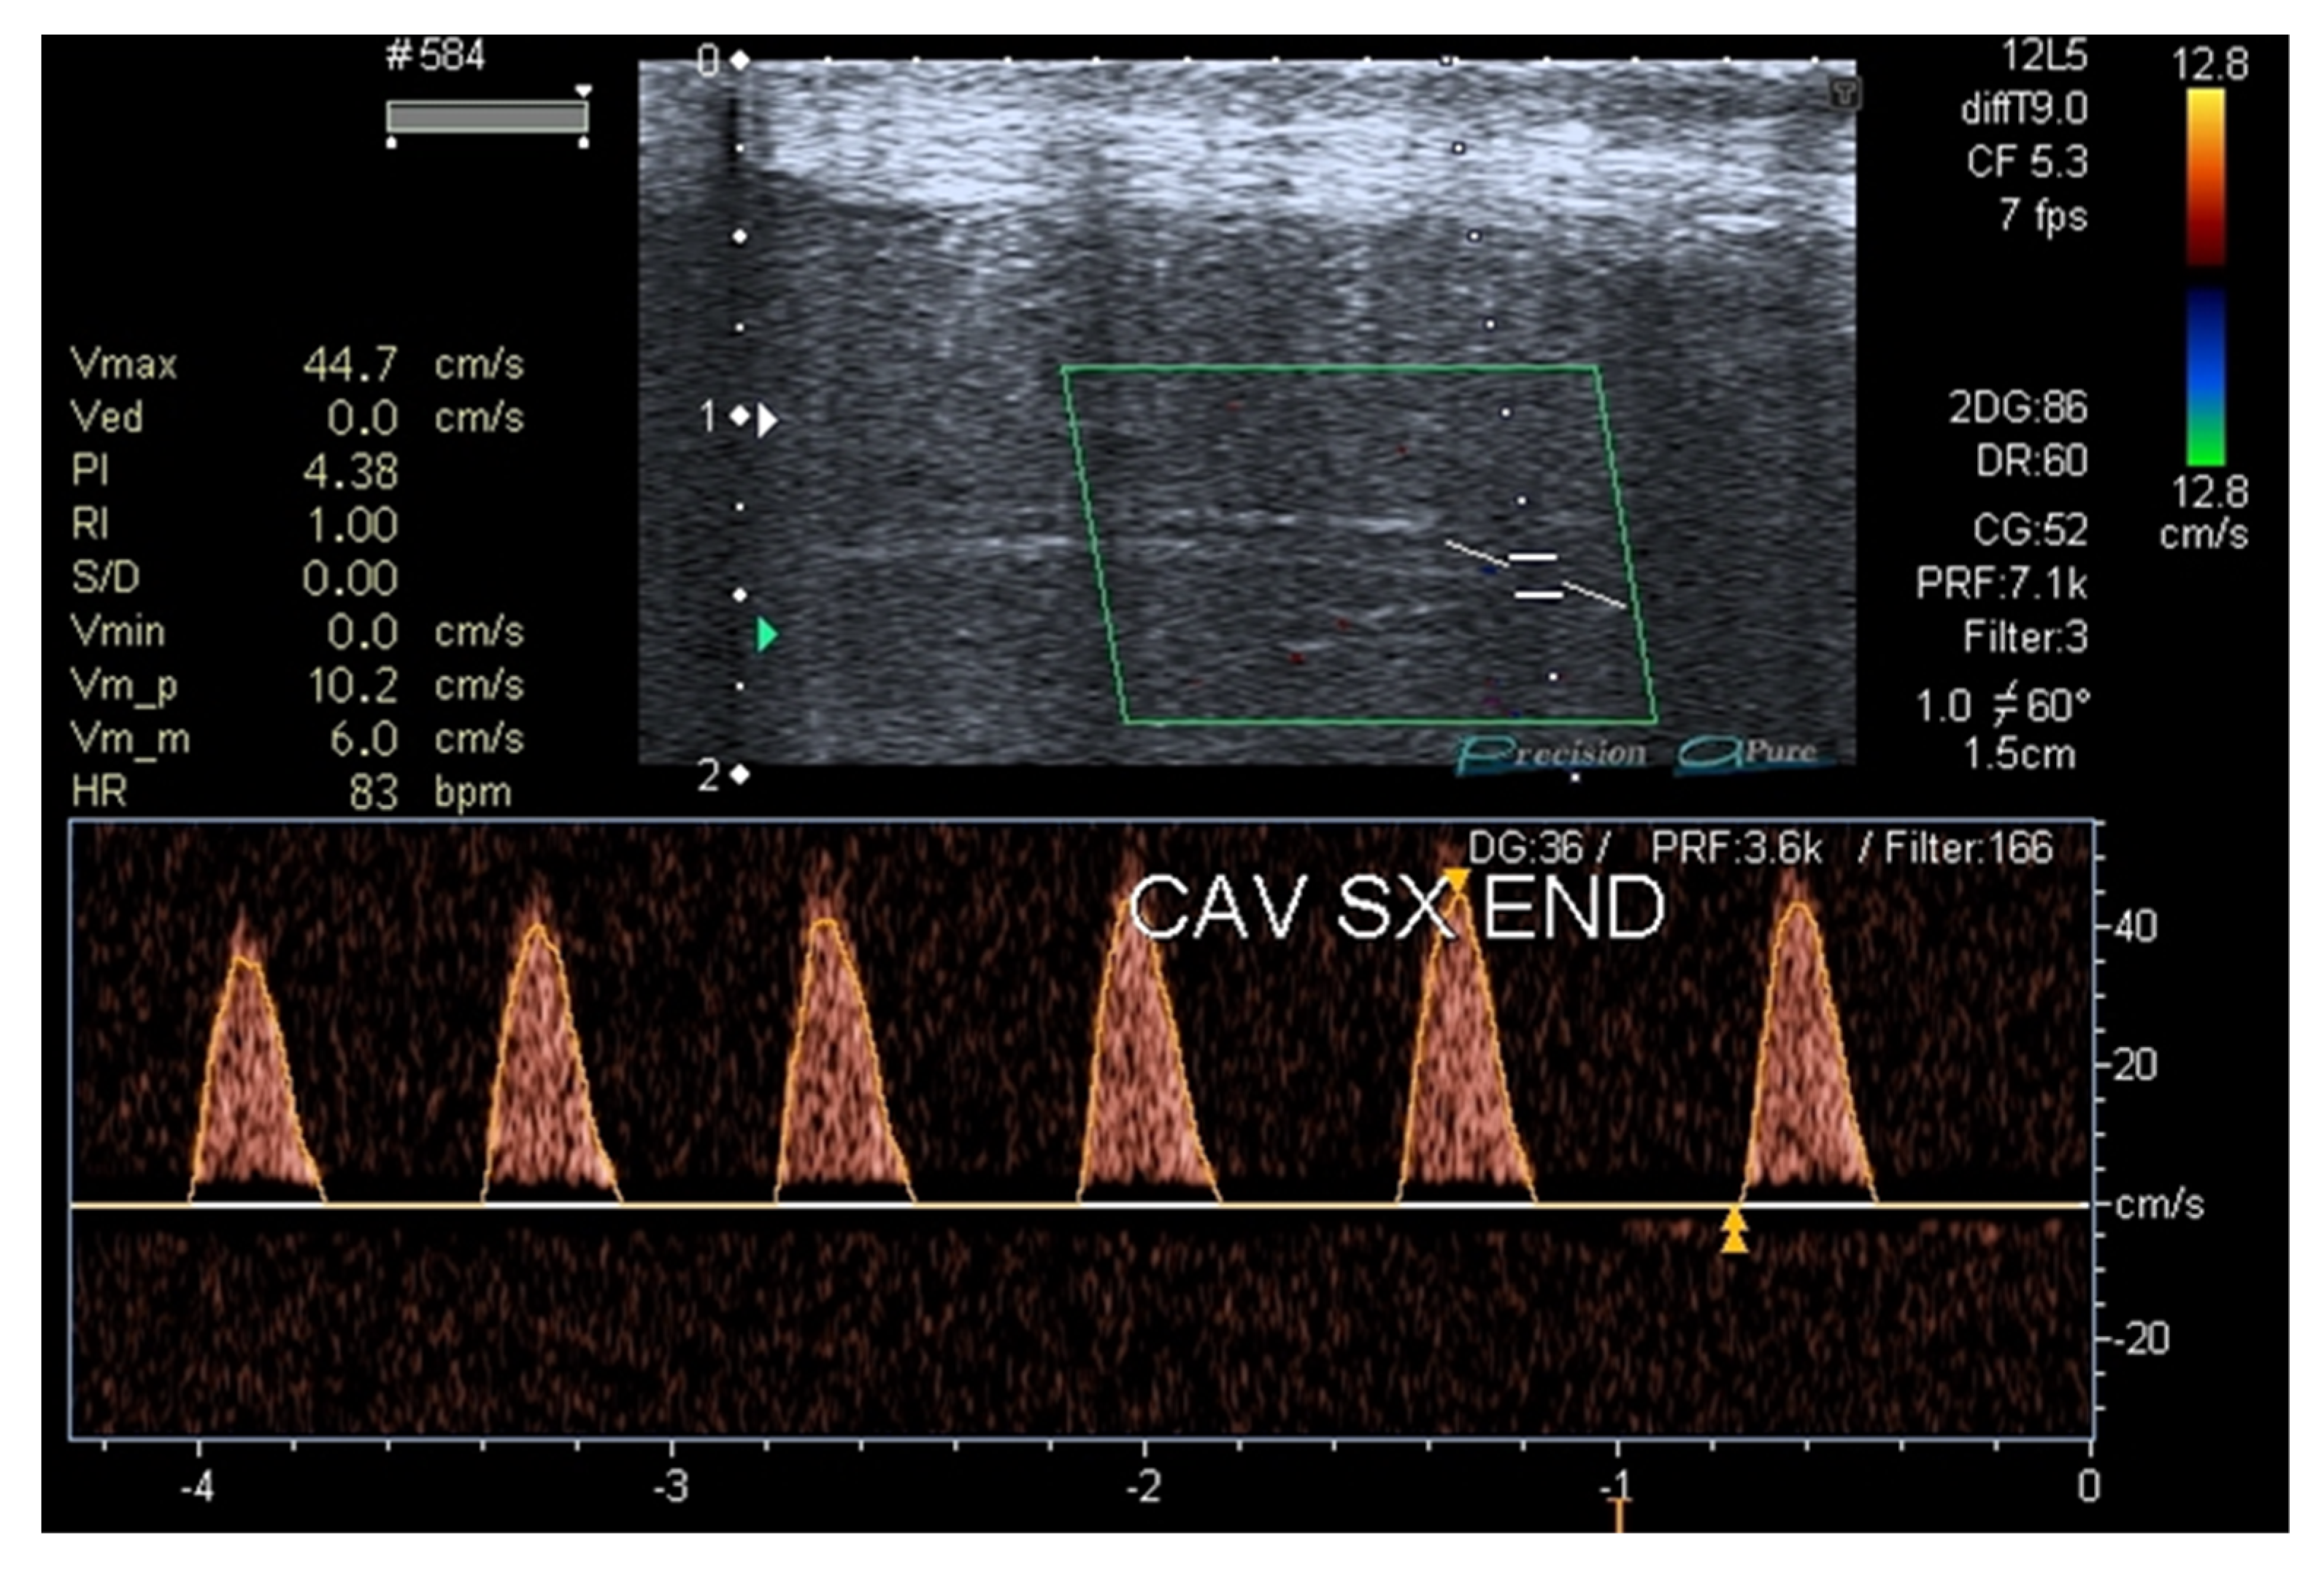

In July 2022 (T3, four months after tadalafil was withdrawn), the patient was re-evaluated, confirming the clinical remission of ED (IIEF5 +2 points) without therapy and the normalization of the inflammation and vascular damage indices. Lastly, a penile duplex ultrasound was repeated after 18 months and a recovery of the penile vascular function was found (Figure 3).

Figure 3.

Penile duplex ultrasound at T3 (18 months after patient’s first visit).

In fact, as seen in many other studies about COVID-19 [50,53], in the case here reported, inflammation markers, such as Endothelin-1 and CRP, were elevated at baseline (four months after COVID-19 remission). We observed a consistent reduction in Endothelin-1 and CRP values after six months and throughout the follow-up period (Table 2). The same improvement was observed in IIEF-5 and SF-36 scores (Table 3) and in the dynamic penile ultrasound performed after 18 months from the first visit (Figure 3).